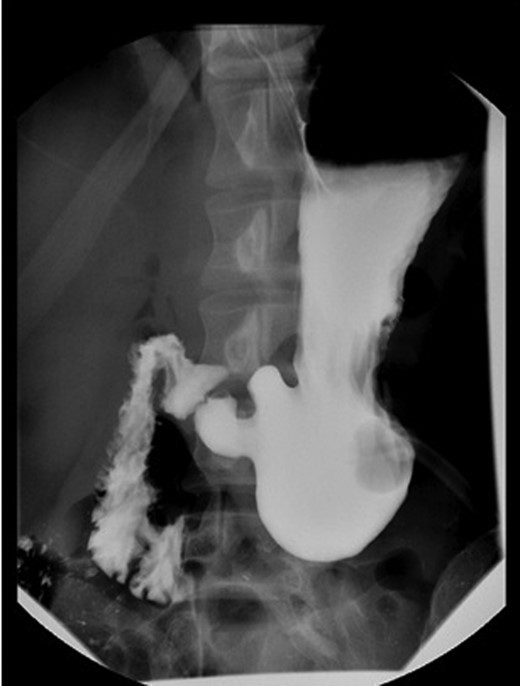

The patient underwent a laparoscopic gastrostomy-tube gastropexy. A 10 mm laparoscope and three 5 mm ports were placed. There was no evidence of a hiatal hernia, diaphragmatic hernia or Meckel's diverticulum on visualization. The patient had healed well from his previous appendectomy. A crease on the stomach was visible where the volvulus had occurred. A 24-French gastrostomy tube was inserted percutaneously into the stomach and inflated. Using the gastrostomy tube, the stomach was approximated to the posterior aspect of the anterior abdominal wall. A point along the greater curve of the stomach, distal to the volvulus, was chosen to suture the stomach to the abdominal wall with permanent sutures. The patient tolerated the surgical procedure well (Fig. 2) and was discharged 4 days later.

Diagnosis is made with clinical suspicion and imaging. X-ray, EGD, CT scan and upper GI contrast study all can be used to visualize a volvulus. An X-ray often shows a retrocardiac air bubble or an expanded air fluid level in the chest, while an upper GI contrast study may reveal an ‘upside-down’ stomach where the pylorus is positioned above the fundus [1, 4, 5]. The preferred treatment for gastric volvulus is repair of the paraesophageal hernia with fundoplication with or without gastropexy. In the absence of diaphragmatic pathology, the preferred treatment is anterior gastropexy whereby the stomach is sutured to the anterior abdominal wall. A tube gastrostomy can be used to further secure the stomach. The procedure can be done either open or laparoscopically. In severe cases where ischemic injury has caused necrosis, gastrectomy may be required [2].